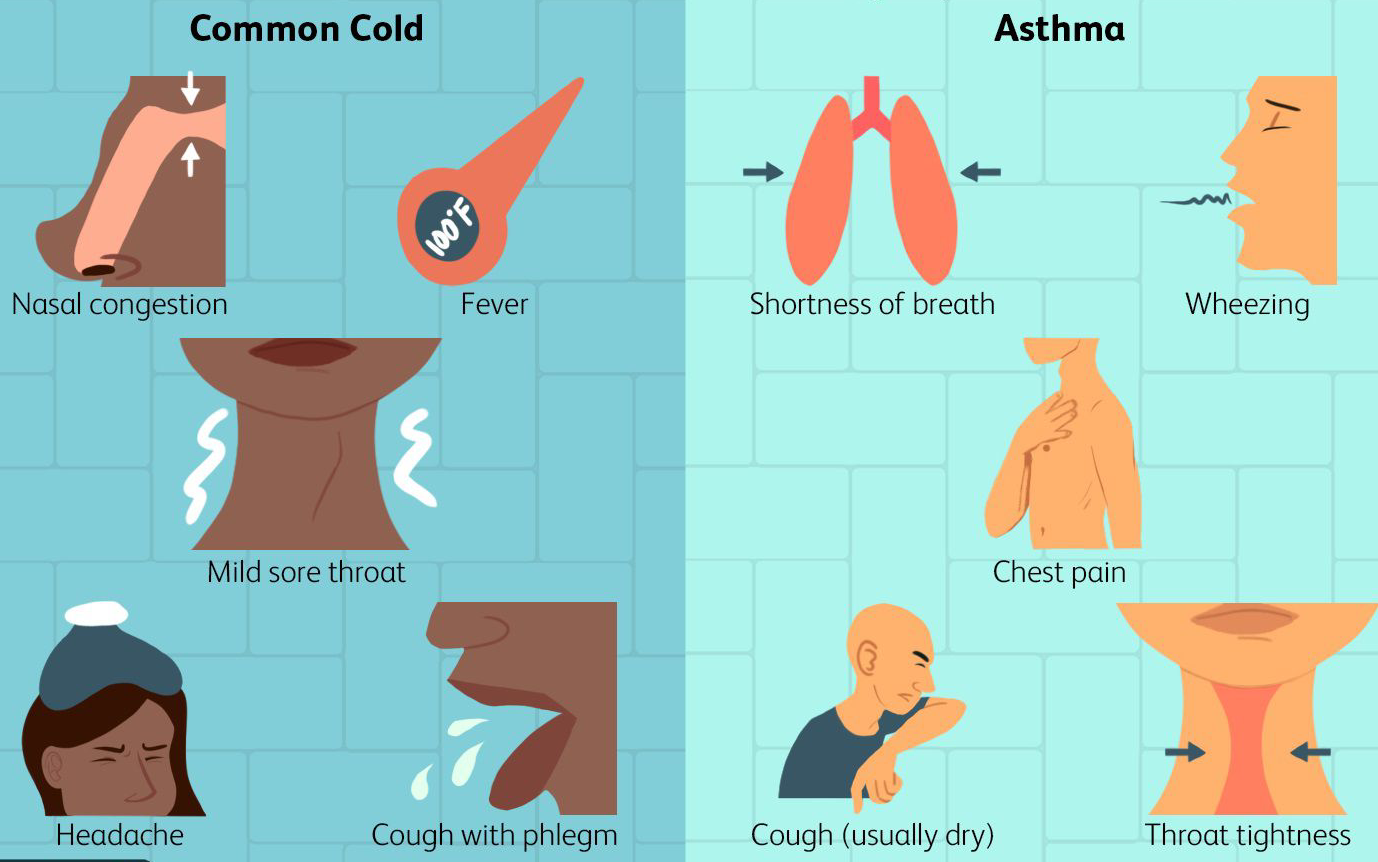

Asthma and cold

Ayurvedic treatment for asthma and cold works by strengthening respiratory health, clearing mucus, and balancing Kapha and Vata doshas using herbal remedies, steam therapy, and dietary changes.